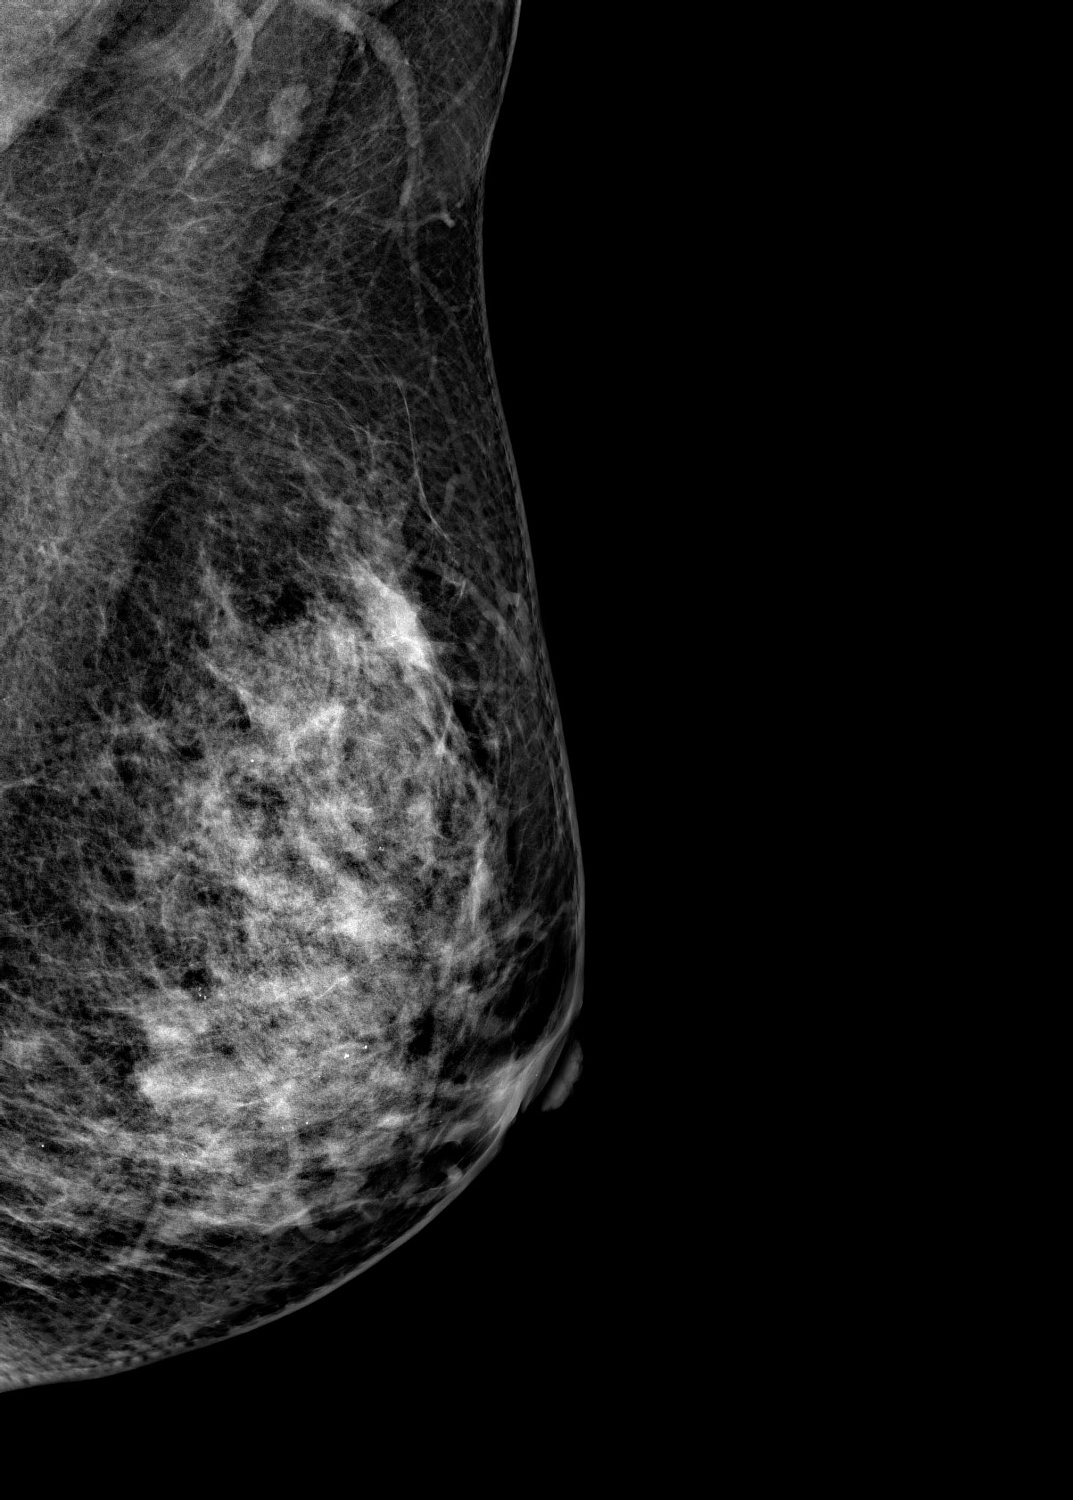

Маммограф выявляет опухоли молочной железы размером от 1-2 мм, которые не определяются при осмотре врача и самообследовании. На снимках хорошо различимы мельчайшие скопления солей кальция (от 87 мкм), тяжистые и другие перестройки тканей, характерные для рака груди 1-2 стадии. Высокую информативность, диагностическую ценность изображений обеспечивает цифровой детектор с самым чувствительным в мире сцинтиллятором. На снимках также определяются воспалительные процессы, кисты и даже небольшие повреждения.

Универсальный размер детектора делает обследование женщин с большим размером груди проще и безопаснее. Функция съемки молочных желез с имплантами позволяет обследовать эту категорию пациенток. На снимках хорошо различимы и ткани груди, и грудные эндопротезы.

Рентгеновский маммограф BRESTIGE EXPERT INDIRECT оснащен чувствительным сенсором непрямого преобразования на основе аморфного кремния. Цифровой детектор этого типа отличается надежностью и обеспечивает высокое качество изображения. Детальная «картинка» получается благодаря активной матрице, содержащей 2816 × 3584 пикселей, и хорошей квантовой эффективности (до 50%). На снимках ясно различимы даже небольшие изменения в структуре тканей и малоконтрастные образования.

Полноформатный детектор облегчает и ускоряет обследование женщин с большими молочными железами, а также делает его безопаснее. Пациенткам с грудью до пятого размера включительно для полноценного исследования достаточно 4 снимков: по 2 для каждой молочной железы. Аппараты, укомплектованные детектором меньшего размера, требуют 8 экспозиций.

Режим позволяет проводить маммографию у пациенток с грудными эндопротезами. На снимках хорошо видны ткани груди. Снимки отражают состояние импланта, в том числе его серьезные повреждения.